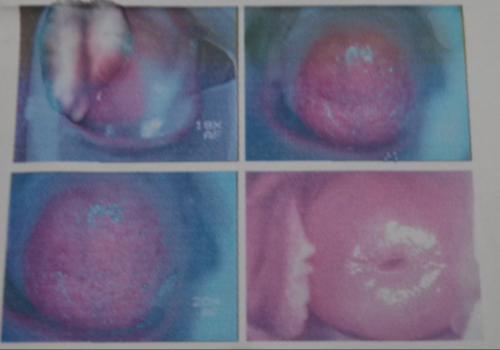

临床常见宫颈糜烂图片

请帮我看看阴道镜检查,宫颈糜烂严不严重.